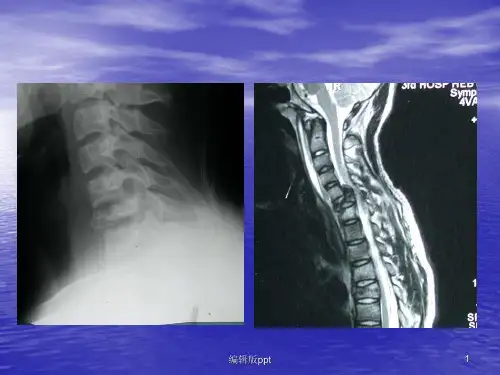

(一)外部结构:脊髓是中枢神经系统组成部分之一, 全长42~45cm,上端于枕骨大孔处与延髓相接,下 端至第一腰椎下缘,占据椎管的2/3。脊髓自上而下 发出31对脊神经,与此相对应也分为31个节段,及8 个颈节(C1-C8),12个胸节(T1-T12),五个腰节 (L1-L5),五个骶节(S1-S5)和一个尾结(Co)。 每个节段有两对神经根-前根和后根,在发育过程中, 脊髓的生长较脊柱生长慢,因此到成人时,脊髓比脊 柱短,其下端位置比相应脊椎高。

了解脊髓节段与椎骨的对应关系,有其重要的临床意义。在 脊髓这种对应关系的推算方法是:上部颈节(C1-C4)大致 与同序数椎骨的椎体相对应;下部颈节(C5-C8)和上部胸 节(T1-T4)与同序数椎骨的上一椎体相对应;中部胸节 (T5-T8)约与同序数椎骨上方第二节椎体相对应;下部胸 节(T9-T12)约与同序数椎骨上方第三节椎体相对应。全部 腰节(L1-L5)约平对第10~12胸椎椎体的范围内。骶节和 尾节(S1-S5、Co)约平对第12胸椎和第1腰椎椎体的范围 内。